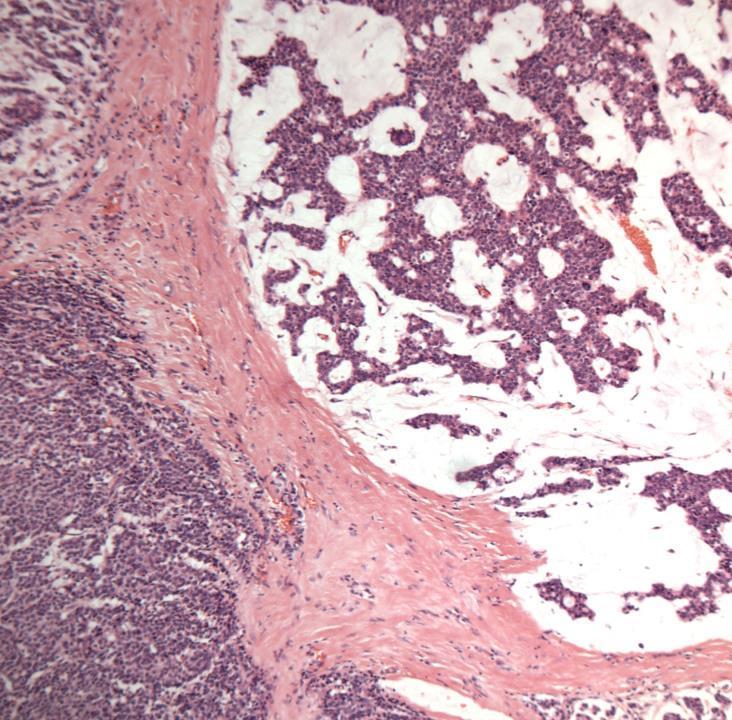

Case 1

◼ Mixed ductal NST and lobular carcinoma with DCIS and LCIS/PLCIS

◼ E-cadherin can be helpful.

❑ Note: e-cadherin can show heterogeneous/aberrant expression.

❑ Beta catenin and p120 can help in difficult cases.